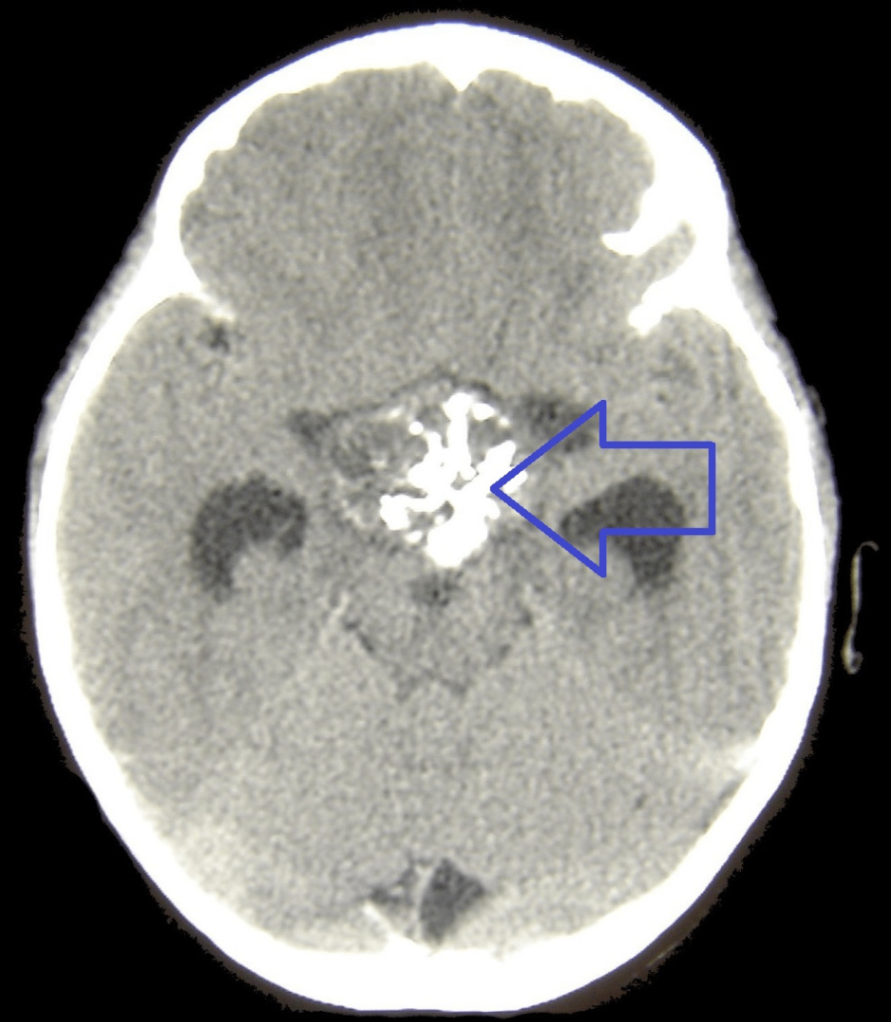

2. 희소돌기아교세포종 (Oligodendroglioma)

1) 분자유전학적 정의

IDH 돌연변이와 함께, 염색체 1p와 19q의 whole-arm co-deletion이 있는 경우로 정의됨

→ 이 조합은 진단적 특징이자 예후가 비교적 좋은 예측인자

2) 병리소견

• 젤라틴처럼 말랑한 회색 종괴로, 내부에 낭종(cyst), 국소 출혈(focal hemorrhage), 석회화(calcification) 자주 동반됨